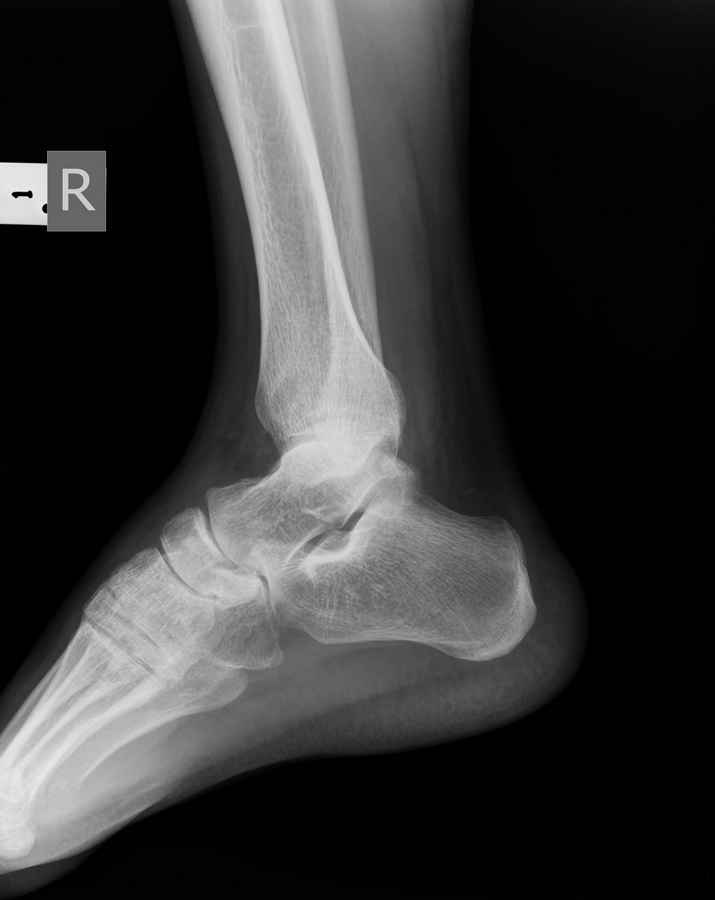

Дорогие коллеги,Мужчина 36 лет, пострадал около 8 месяцев назад в ДТП (водитель мотоцикла).

Подтаранный вывих лечили гипсовой лонгетой. Недиагностированным остался перелом ладьевидной кости, который беспокоит в настоящее время. Аваскулярный некроз кости, похоже. Добавил наиболее значимые снимки, на мой взгляд.

По данным снимкам однозначно сказать о некрозе ладьевидной кости нельзя. Типичные изменения при аваскулярном некрозе ладьевидной кости, как правило, начинаются в центральной её части с дальнейшим развитием коллапса. В данном случае в значительной степени пострадал таранно-ладьевидный сустав, вероятнее всего, именно это является причиной болевого синдрома. При отсутствии эффекта от физиотерапии и ношения ортопедической обуви в течение ближайших 6 месяцев придётся ставить вопрос о таранно-ладьевидном артродезе.